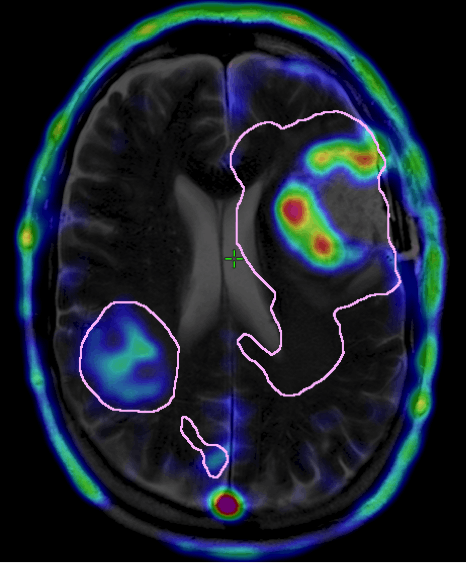

- CT Scan

- MRI (higher resolution than CT)

A CT scan is often the first diagnostic test ordered if a brain problem is suspected as they are cheap and readily available. A dye (contrast) can be injected to better define what is happening in the brain (blood vessels).

An MRI is typically performed if the CT shows an abnormality. MRI scans generally provide a more detailed picture of the brain and its structures. Again, contrast can be added to a MRI scan to increase clarity.